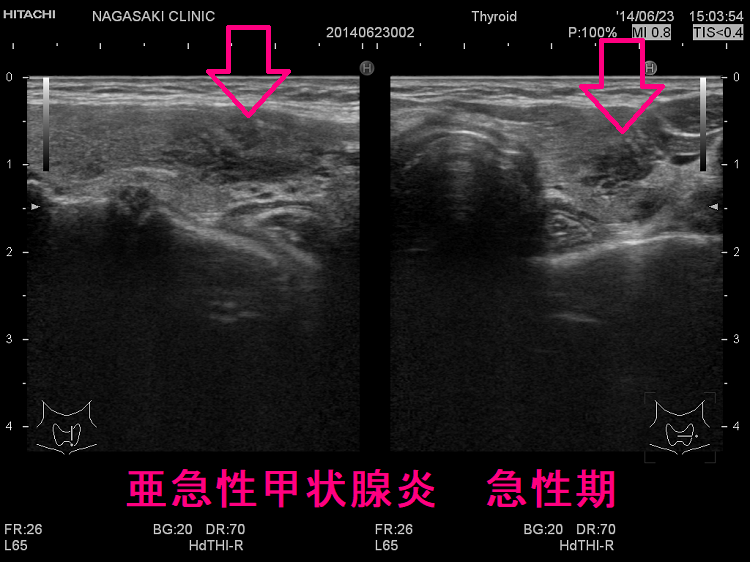

長崎甲状腺クリニック(大阪)オリジナルの亜急性甲状腺炎の治療は、中途再燃・再発を防ぐため、超音波(エコー)検査で炎症範囲を毎回調べ、改善度に応じてステロイド量を調整。炎症の強い部分は黒く、血流乏しく、エラストグラフィーで青くなる。副作用チェックはステロイド肝障害・膵炎・筋障害・低カリウム血症・糖尿病。甲状腺乳頭癌の合併、亜急性甲状腺炎ではなく、甲状腺乳頭癌の事も。亜急性甲状腺炎はバセドウ病,橋本病に合併、あるいは誘発する事も。頚部腫大、甲状腺中毒症が先行する場合、エコー検査で偶然見つかる事も。数年かかっても完全治癒しない亜急性甲状腺炎も稀に存在。

下は亜急性甲状腺炎の超音波(エコー)画像で、炎症の強い部分は黒く、エラストグラフィーでは青くなります。